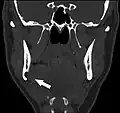

Stafne bone cavity seen on coronal CT Stafne bone cavity seen on coronal CT